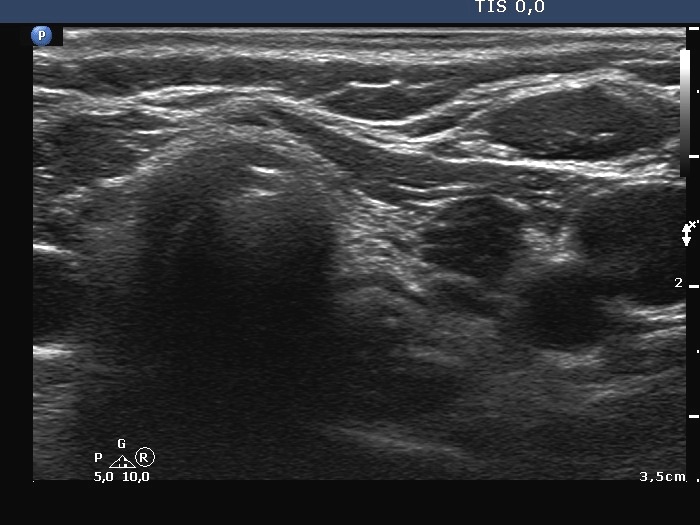

Ultrasonography. The thyroid was hypoechogenic and atrophic. The left lobe was composed of hypoechogenic areas partly divided by connective tissue. There were no nodules of pathological sense in the thyroid.